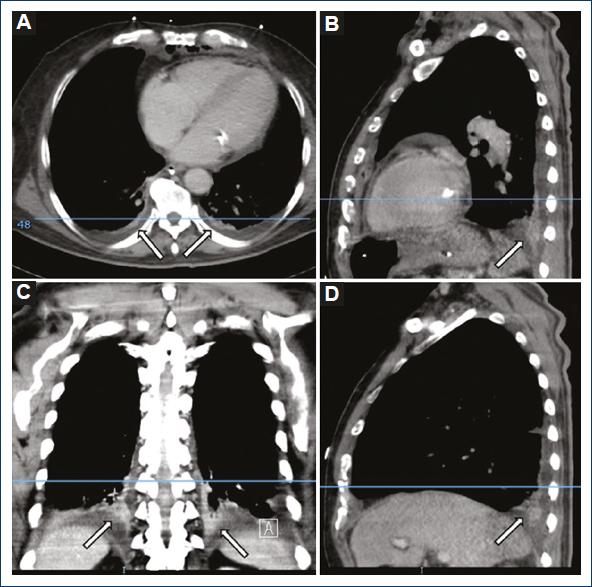

We evaluated 25 patients that we operated to drain the mediastinum for the diagnosis of mediastinitis, following the Estrera and Endo criteria, at the Hospital General de México “Dr. Eduardo Liceaga,” from August 1 2018 to July 31 2019. Ten (40%) were female patients and 15 (60%) were male patients. Twenty-one (84%) patients showed atelectasis and 4 (16%) did not have atelectasis. Of the patients that showed atelectasis, 17 (81%) were bilateral, 2 (9.5%) were right sided, and 2 (9.5%) were left sided. We also analyzed the occurrence of pleural effusion in this group. Fifteen (60%) patients had pleural effusion and 10 (40%) did not. Of the total patients with pleural effusion 11 (73.3%) were bilateral, 3 (20%) of the right side, and 1 (6.6%) of the left side (Figs. 1-3).

Figure 2 Patient with basal posterior segments atelectasis showing pleural effusion. A: axial plane. B: sagittal plane left hemithorax. C: coronal plane. D: sagittal plane right hemithorax.